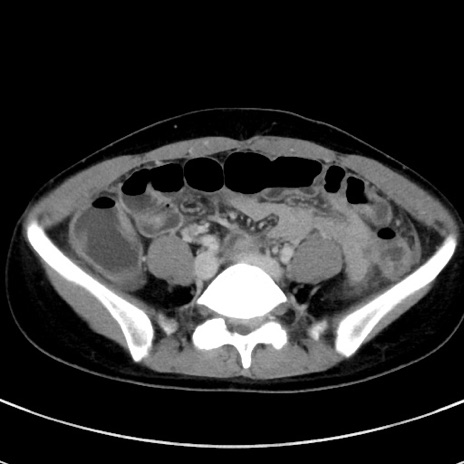

症例17(横断像)

【症例】20歳代女性

【主訴】嘔吐、下腹部痛

【現病歴】昨日夕食後に嘔吐し下腹部痛が出現。本日になっても嘔吐持続し改善しないため来院。

【身体所見】意識清明、BT 37.2℃、BP 108/67mmHg、腹部:平坦、やや硬、下腹部正中から右にかけて圧痛あり、反跳痛軽度あり、tapping pain(+)。

【データ】WBC 13600、CRP 14.94